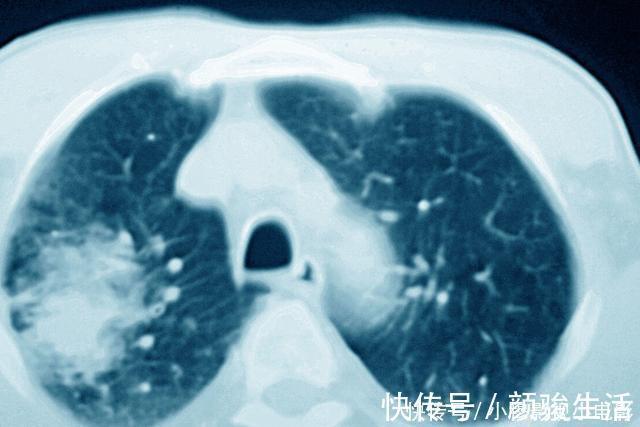

作用三:对某些癌症,可以评估治疗效果。

对于有的癌症,CT还能够起到评估治疗效果的作用;有的癌症患者,在发现的时候已经没有了手术治疗的机会;也有的癌症,本身就不适合手术治疗,这个时候可能就需要放化疗等其他的治疗方法来治疗癌症。那么对于这些治疗方法,往往评估疗效非常重要的办法就是进行CT检查。

比如淋巴瘤,大部分淋巴瘤患者都是没有办法进行手术切除的,主要的治疗方法是化疗和放疗。而在进行化疗之后,医生需要判断化疗的效果,这个时候往往就需要结合CT检查,通过CT检查,了解病灶有没有缩小、减少,如果病灶出现了缩小、减少,那么说明治疗有效果,而如果复查病灶没有明显的变化,那么则说明化疗效果不佳,可能需要调整治疗方案。

另外,有的癌症可能一开始没有办法手术,但是可以先通过放化疗,把病灶缩小,然后再进行手术治疗,那么这其中也是需要通过CT检查来评估病灶情况,了解是否可以手术。